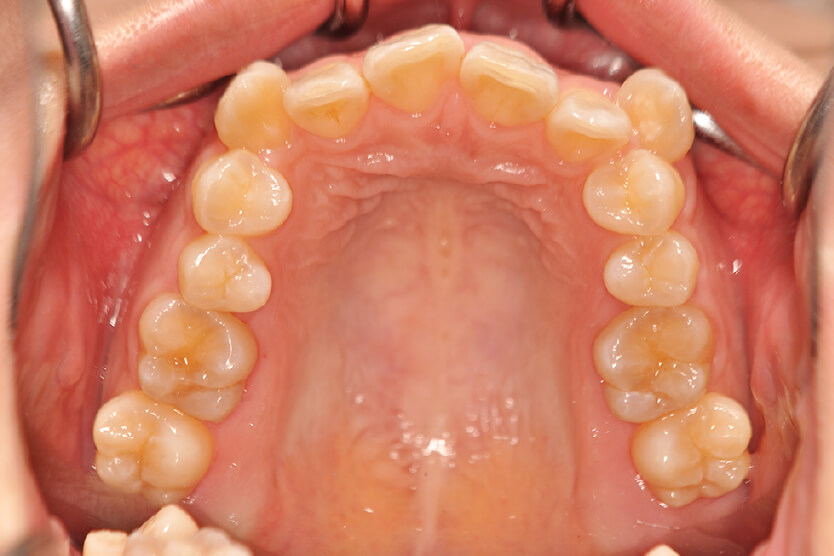

| 治療内容の詳細 | 初診時21歳の女性で、八重歯、歯のがたつき主訴として来院されました。 検査の結果、上下顎前歯部叢生を伴うアングルⅡ級1類不正咬合と診断しました。 治療としては、上下顎左右第一小臼歯を抜歯し、セルフライゲーションブラケット装置(デーモンシステム)とマウスピース矯正装置(インビザライン)で歯の配列を行いました。 治療期間は、1年4か月でした。 |